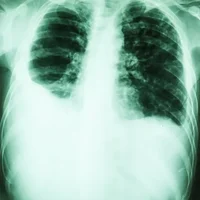

Diagnostic : le diagnostic de la pneumonie peut être posé à l'aide de plusieurs méthodes, notamment :

• Radiographie thoracique pour visualiser les zones affectées des poumons.